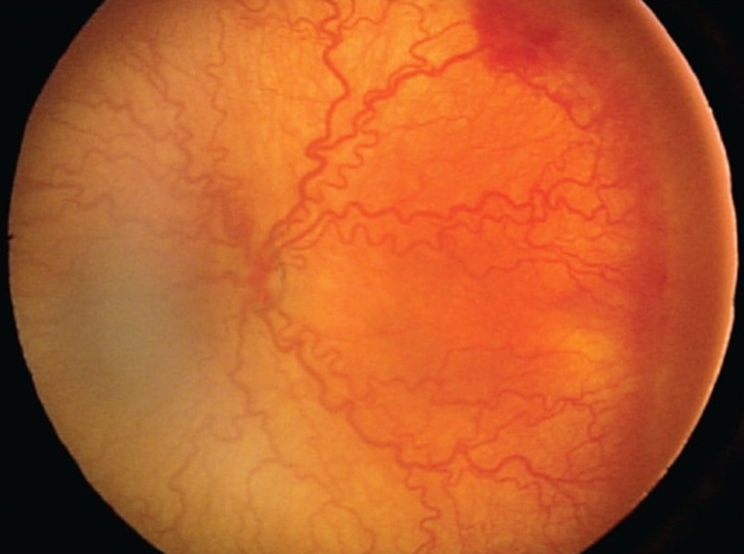

- 미숙아망막병증

미숙아망막병증은 망막혈관의 이상으로 미숙아에서 발생하는 질환으로 소아 실명의 가장 중요한 원인을 차지하고 있습니다. 최근 의학의 발전과 더불어 미숙아의 생존율이 높아지면서 미숙아망막병증의 발생률도 증가하고 있습니다.

이른 출생으로 인해 자궁 내의 환경보다 상대적으로 산소 분압이 높은 고산소환경과 모체로부터 전달되는 혈관형성인자의 결핍이 원인입니다. 전체 미숙아 중 약 20~30% 내외에서 발생하며, 자연경과 중 대부분 저절로 퇴행하고 6% 정도에서만 치료가 필요한 심한 망막병증으로 진행합니다. 이 경우 신생혈관이 증식하고 종래에는 견인망막박리가 발생할 수 있습니다.